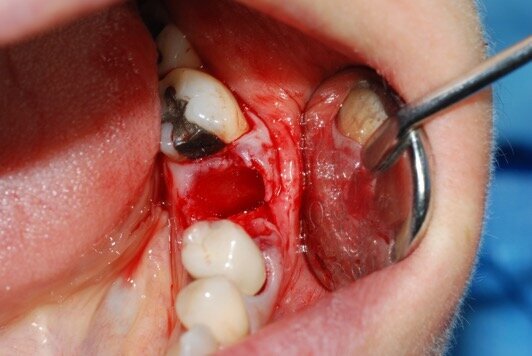

I lembi sono stati poi suturati a livello dell’osso (Gore-Tex®, 4.0, Gore, Newark/ NJ, USA) senza la necessità di ottenere una chiusura completa (Fig. 3). In fase postoperatoria è stato prescritto un antinfiammatorio (Nimesulide 100 mg, 2 volte al giorno per 3 giorni), un analgesico (Paracetamolo 500 mg, 1 compressa ogni 8 ore per 3 giorni) e clorexidina 0.12%, e fornita istruzione completa all’igiene orale. La sutura è stata rimossa dopo 10 giorni. A 3 e a 6 mesi sono state eseguite le radiografie periapicali parallele.